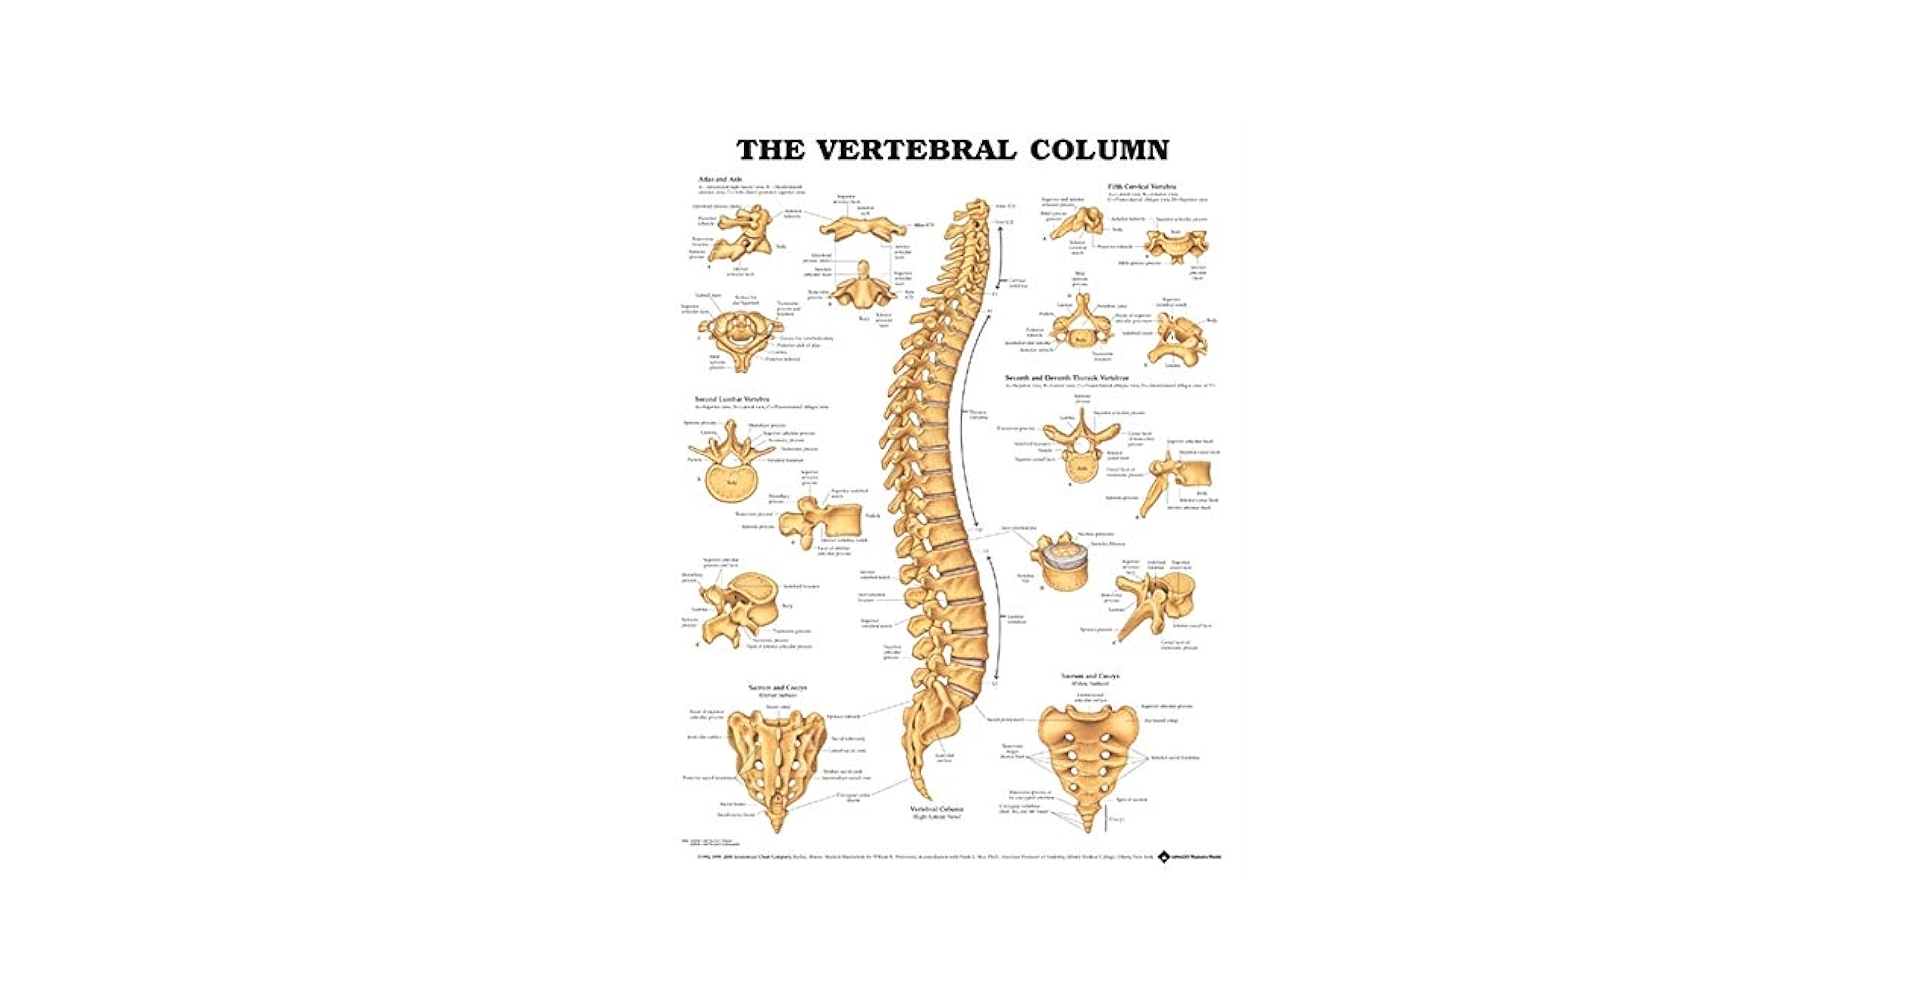

The Vertebral Column Anatomical Chart is a detailed illustration that breaks down the spine into its individual components. From the cervical spine in the neck to the coccyx at the base, each vertebra plays a unique role in supporting the body and allowing for movement.

By studying the Vertebral Column Anatomical Chart, healthcare professionals, students, and individuals can learn about the different regions of the spine, including the curvature of the vertebrae, the function of intervertebral discs, and the role of spinal nerves in transmitting signals throughout the body.

Whether you’re a medical professional looking to enhance your knowledge or someone curious about the inner workings of the human body, exploring the Vertebral Column Anatomical Chart can offer valuable insights into the complexities of the spine.

Next time you have a chance, take a closer look at a Vertebral Column Anatomical Chart and marvel at the intricacies of the spine. You’ll gain a newfound appreciation for this essential part of the body and the role it plays in keeping us upright and mobile.

The Vertebral Column Anatomical Chart Amazon